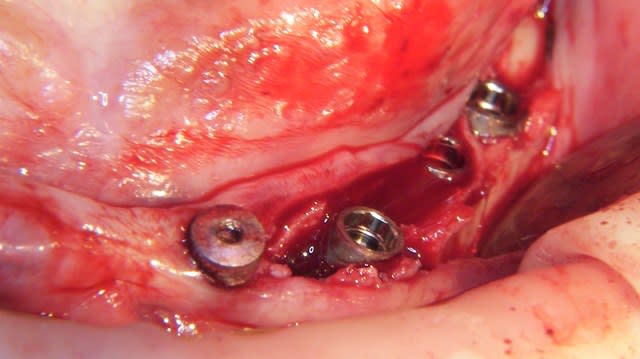

Un exemple de splitting sectoriel au maxillaire sup avec :

- piezo,

- osteotome,

- implant Astra osseospeed,

- comblement par mélange os autogène et BioOss,

- recouvrement par membrane BioGide + conjonctif palatin.

Très juste Dumaille. Le lambeau est d'épaisseur totale d'une part au niveau des incisions crestales verticales et sur toute leur hauteur et d'autre part jusqu'á la moitié de la hauteur du volet osseux. Le reste est en épaisseur partielle. Point important. Merci de l'avoir souligné.

Effectivement Growler, la crête atrophique à la mandibule est souvent dense (type 1 à 2); il est difficile réaliser une mobilisation du volet vestibulaire avec les seuls osteotomes. Pour augmenter l'élasticité du volet osseux vestibulaire, une incision longitudinale basale de décharge es très souvent nécessaire en plus des incisions verticales et crestale. Cette incision longitudinale augmente la résilience et soulage la mobilisation du volet osseux vestibulaire. Ce dernier peut très facilement après mobilisation être transvissé et fixé par des vis d'osteosynthèses classiques.

Il est à mon avis préférable d'obtenir un trait de fracture propre et maitrisé plutôt qu'un volet vestibulaire fragilisé, traumatisé et abimé.